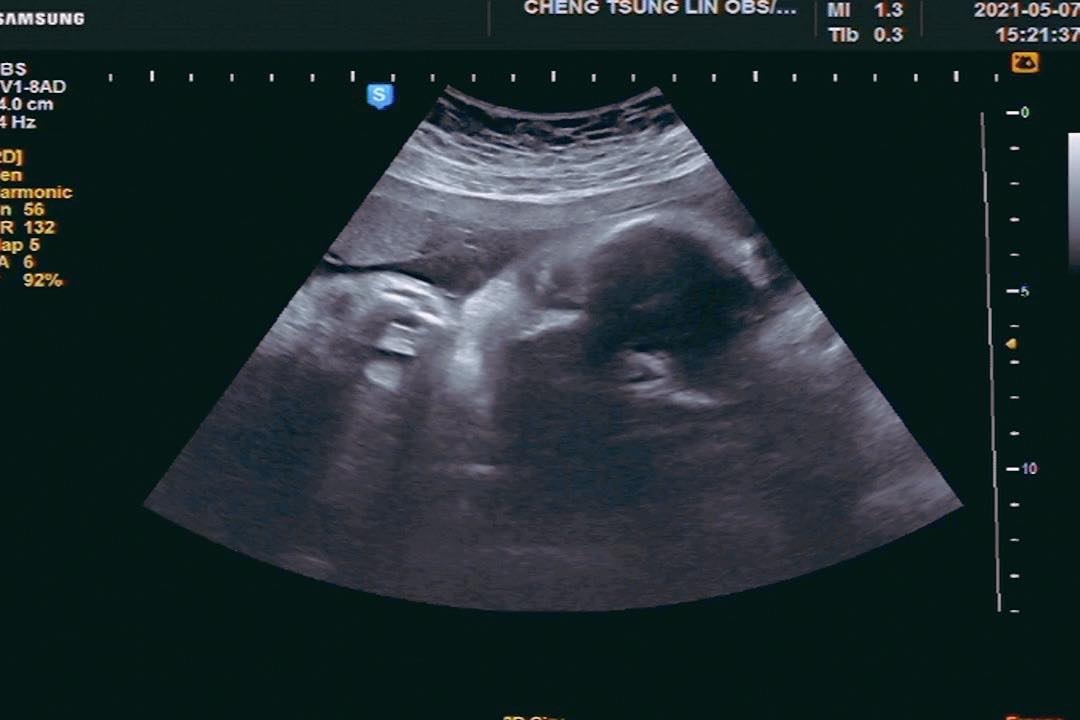

沒想到今日就傳出喜訊,小甜甜順利產下3000多克女兒「米苔目」,而據小甜甜經紀人提供的照片可以看出小甜甜產後狀態良好、寶寶看起來也相當可愛健康。